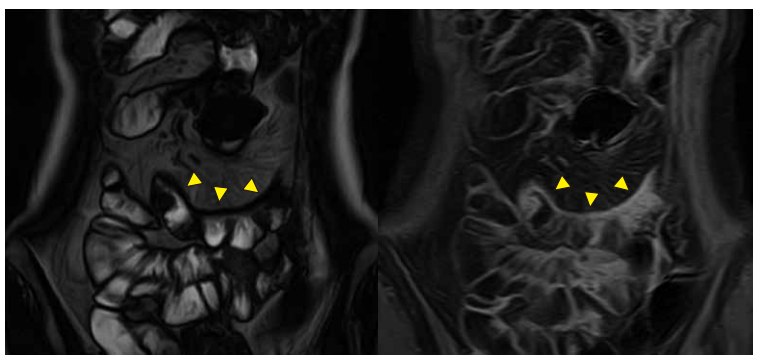

MRエンテログラフィー 1

縦走潰瘍。弧状変形を伴い、腸間膜の脈管は増強されcomb signを呈している。造影では縦走潰瘍部が増強されている。